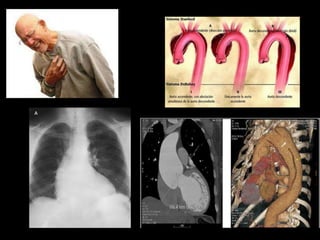

 Disección aórtica.

DISECCION DE AORTA

LOS 5 GRANDES Síndromes coronarios agudos.  Disección aórtica.  Embolismo pulmonar.  Neumotórax a tensión.  Ruptura esofágica.